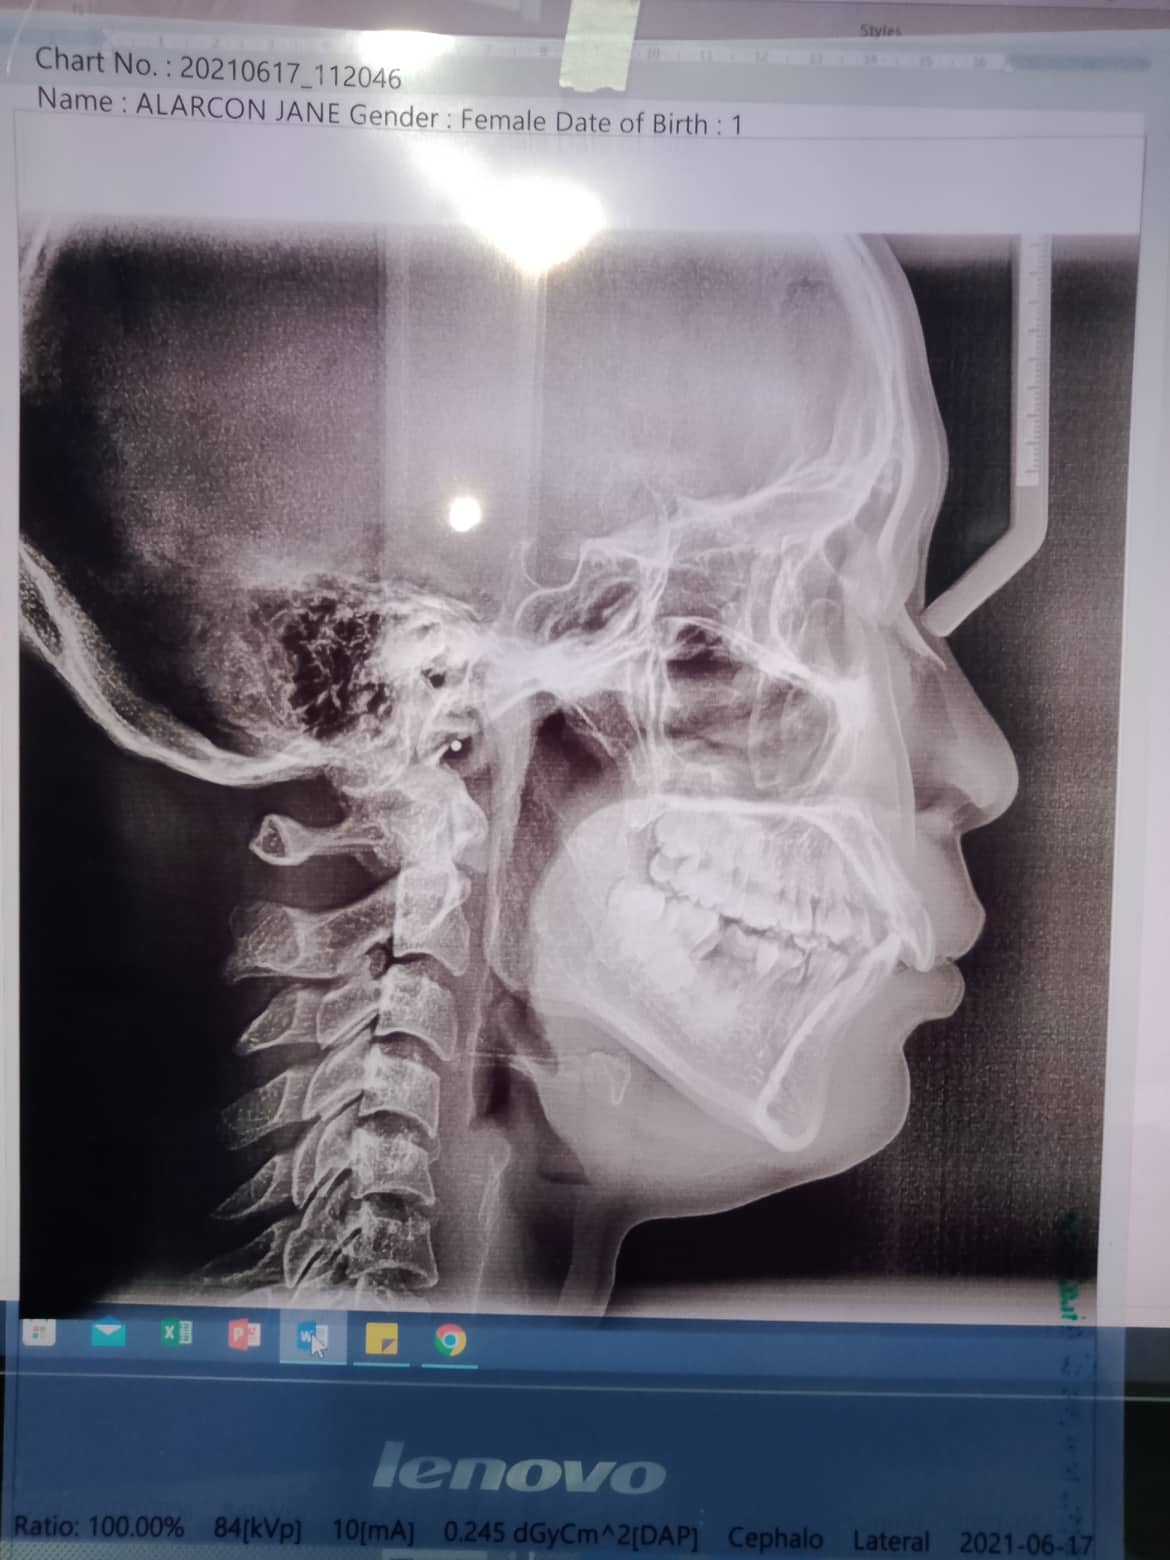

Edit Record Check our patient data records. Add patient information Patient Info Profile picture Last Name First Name Middle Name Birthdate Age Street Barangay City Country Zip Code Contact number Email Procedure 07/27/21- U16niti/ L14niti RW 11/21 09/08/21 - 16niti U/16nitiL 10/8/21- 16ss U/L upper to left/ move 34 towards mesial 11/12/21- 16ssUL/ #35 installed- to upright double wire 14niti 1/7/22- same wire/ S- elastic L button 35 to 24-25- fox 02/25/22- close space on 13-12 ***for reshape 35 one side right elastic loop to 45 04/02/22- reshape 35 with fiber same wire. RPI 13 and 23. distalize 05/06/22- 16 ss U/ 18 niti L/ class 2 elastic rabbit 06/18/22- same wire/ class 2 right chimunk/ left rabbit 08/06/22 - same wire/ Class 2 elastic chimunk 09/24/22- 16ss L/ same wire upper. class 2 rabbit 11/18/22- adj 01/07/23- ADJ 04/1/23- 16x16 ss UL chain Upper/ intrude #21 05/26/23- U: 16ss wire, 22-12 individual, chain 26-16 L: same wire; individual / Rabbit elastics 06/30/23- 16x22 UL Upper chain 26 occlusal deepseated caries with CAOH 08/17/23 -same wire chain upper individual lower for removal oct-nov 09/29/23- UL legature wire.. **** For removal for October *** 01/13/24 brace removal 08/03/24 Exo #38 gel foam suture ozone 04/09/25 OP File 302095548_384062630396548_1908952325740404096_n.jpg File 2 302234576_799187434601578_178624593392175074_n.jpg File 3 File 4 File 5 File 6 File 7 File 8 File 9 File 10 File 11 File 12 File 13 File 14 File 15 File 16 File 17 File 18 File 19 File 20 Retain Record Retain Record Yes No Save Your Changes